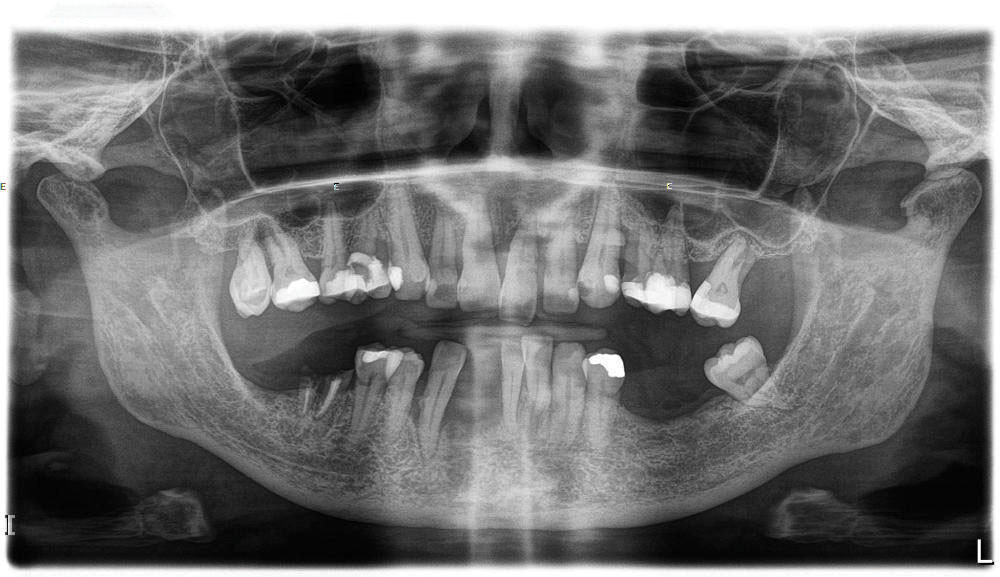

Fig 11. Initial panoramic radiograph.

Figure 11

A 60-year-old female patient presented with many periodontally and restoratively hopeless teeth that severely compromised esthetics and function and were inadequate to retain a maxillary restoration. She declined to advance into a full maxillary denture or partial denture. Existing maxillary teeth included Nos. 2 and 4 through 14 (Figure 9 and Figure 10). The opposing dentition was stable. The patient was in good health with no allergies to medication.

At the initial visit, a panoramic x-ray (Figure 11) and periapical x-rays were taken. The patient was photographed to capture her full face and shoulders, and a digital scan of the maxillary dentition was obtained. This file was electronically sent to the implant company to complete the VSD.